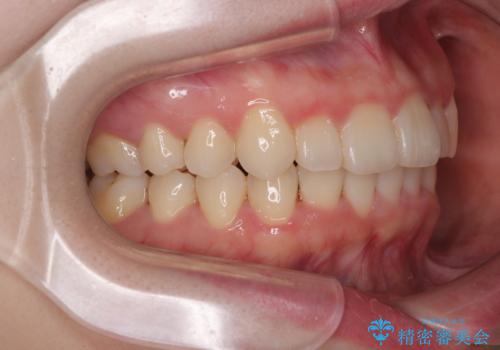

- 上下前歯のデコボコを気にして来院された患者様です。

マウスピースでもワイヤー装置でも対応可能でしたが、右側の咬み合わせが上顎がやや前方に位置していることから、補助装置を使用することが推奨されました。

自己管理の煩わしさを気にして、補助装置併用によるワイヤー装置での矯正治療を行うこととしました。

右上と左下の第一大臼歯2本が周辺の歯と比べて位置がずれていたため、ゴムかけやワイヤーに曲げを入れることで移動を試みましたが、どうよら癒着をしており、移動困難と判断されました。

見た目や咬み合わせに違和感がないとのことで、癒着歯の無理な移動は試みずに治療を終えることとしました。